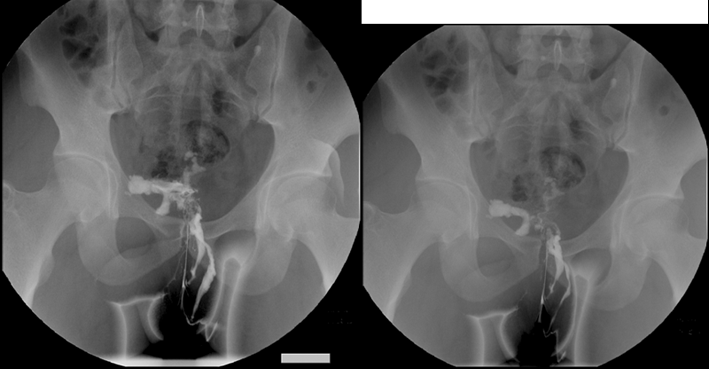

道不规则性窦道影